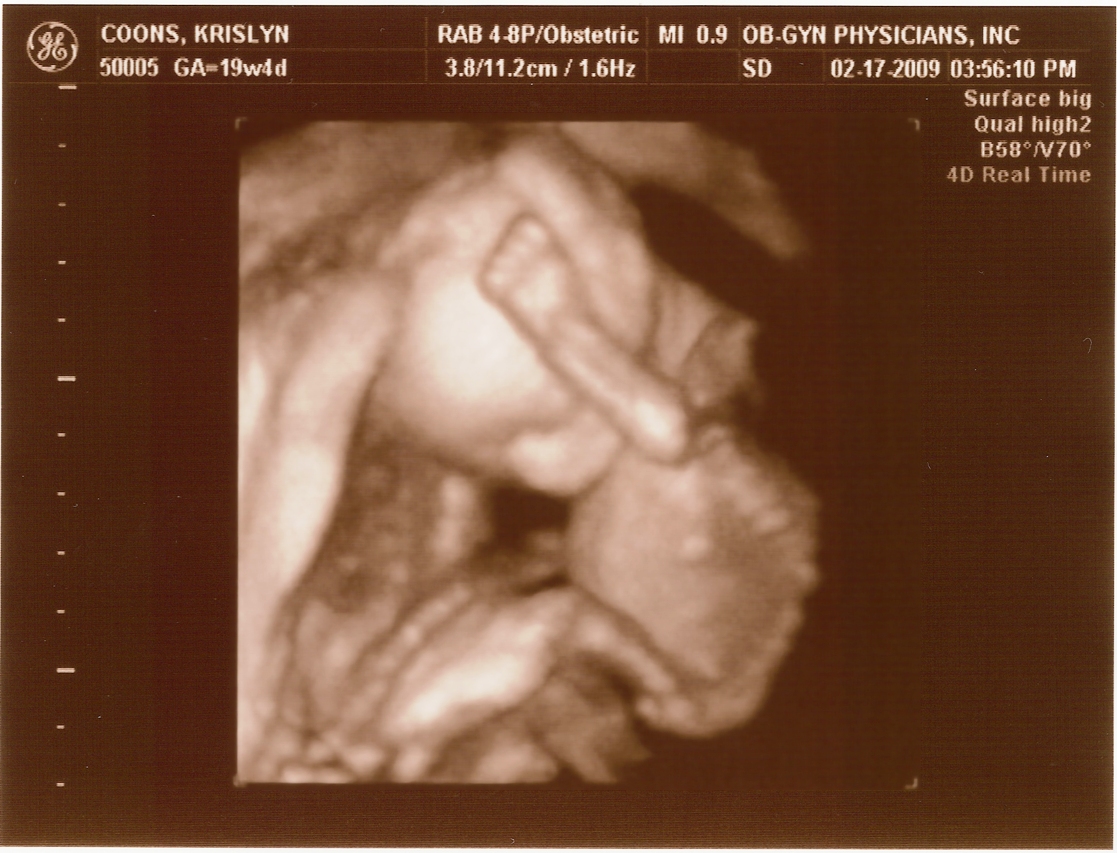

Ultrasound Pictures

20 weeks -

Arm & Head